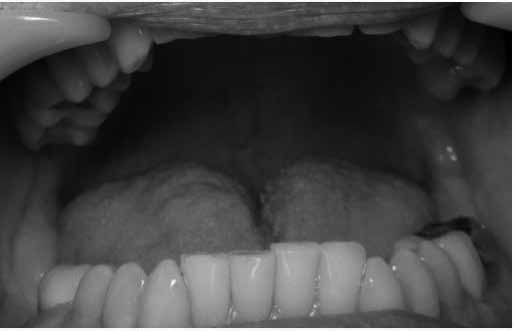

Oral evaluation demonstrated Mallampati class 4, furrowed tongue, coating of the tongue (indicating mouth breathing from nasal obstruction), and scalloping of the tongue, which are both indicative of a sleeprelated breathing disorder, see Figures 4 and 5.